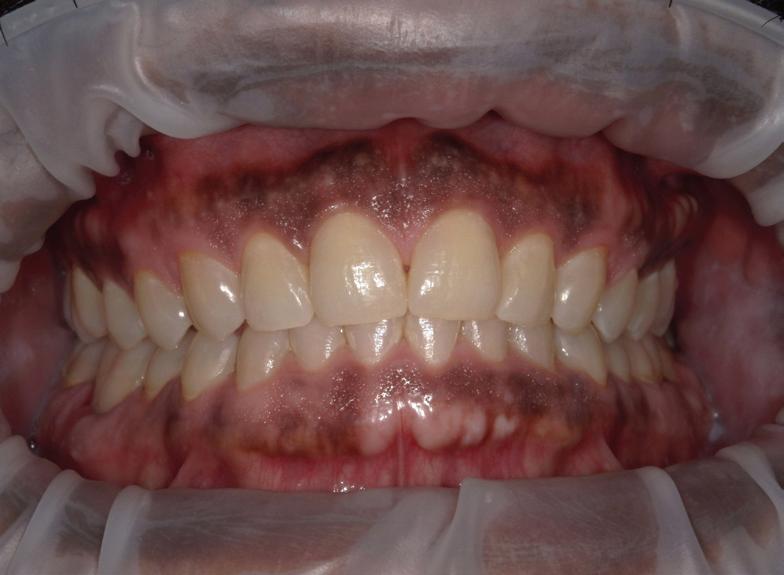

57 | Cosmetic Dentistry | Submitted by E. Taylor Meiser, DDS

By Karl A. Smith, DDS, MS

Hollywood stars know the power of a beautiful smile. Celebrities seem to have perfect teeth, but just like the rest of us, they’ve had a little help from their dentist.

If periodontal tooth and gum issues are not treated in advance of beautiful cosmetics, you may be wasting your time and money. Periodontics are the foundation of a healthy smile and can make the money you spend on beautiful teeth last many years longer.

Opened wide in a positive way, your smile can help make new friends, close a business deal, cheer up a broken heart and ensure that other people feel good about you. How you feel about your smile, directly relates to how much you actually use it.

Do you like your smile? If not, you may be missing out on a beautiful and healthy smile that will give you the self-confidence you deserve. And, it goes one step further, healthy teeth and gums are the foundation of a healthy body – as your oral health directly impacts your overall health.

Advanced dentistry and good periodontal (gum) care can help you achieve the ultimate show-stopping smile. Dental implants will give you back your smile with natural looking and fully functional teeth that best replace your own. Gum grafting can reduce a “gummy smile” to show more of your teeth and open up your beautiful smile.

Laser treatments that utilize less invasive procedures can control and eliminate periodontal disease to help save your natural teeth and gums. An experienced periodontist can provide you with countless options for improving your smile and keeping your gums and teeth healthy for life.

The effect of a missing tooth is not only devastating to your smile, but it’s detrimental to your long-term oral and medical health. It’s not just about unsightly gaps; people missing teeth lose supportive gum tissue and the bone that surrounds other teeth, and eventually the supporting bone in the jaw begins to dissolve. Studies show that people with all of their teeth can live on average 10 years longer than people with missing teeth.

Having gaps where teeth are missing affects the way the jaw closes as the remaining teeth begin to tilt and drift into the gaps. Food can become trapped in these spaces, increasing the risk of decay and gum disease. The tilting and drifting can also cause problems for the opposing teeth as your bite becomes off-balanced and you may begin to experience jaw and joint problems.

Without the support of your teeth and facial bones, your face will begin

to look prematurely aged. Lost teeth affect what you eat and how you swallow and process food and how you speak and function on a daily basis.

The good news is that an experienced periodontist has the advanced training beyond their regular dental degree to prevent, diagnose and treat periodontal (gum) disease with the most advanced laser therapy to help keep your smile healthy and beautiful. A periodontist can also offer personalized solutions to replace your

missing teeth, repair your damaged gums, and prevent or rebuild bone that may have been lost.

Your teeth provide much more function than just the ability to chew. They are necessary for the health of the gum and jaw tissues as they provide a strong foundation for a truly beautiful smile. Take control of your preventative dental health. Make an appointment for a complete periodontal evaluation with an experienced periodontist today. You will be glad you did.